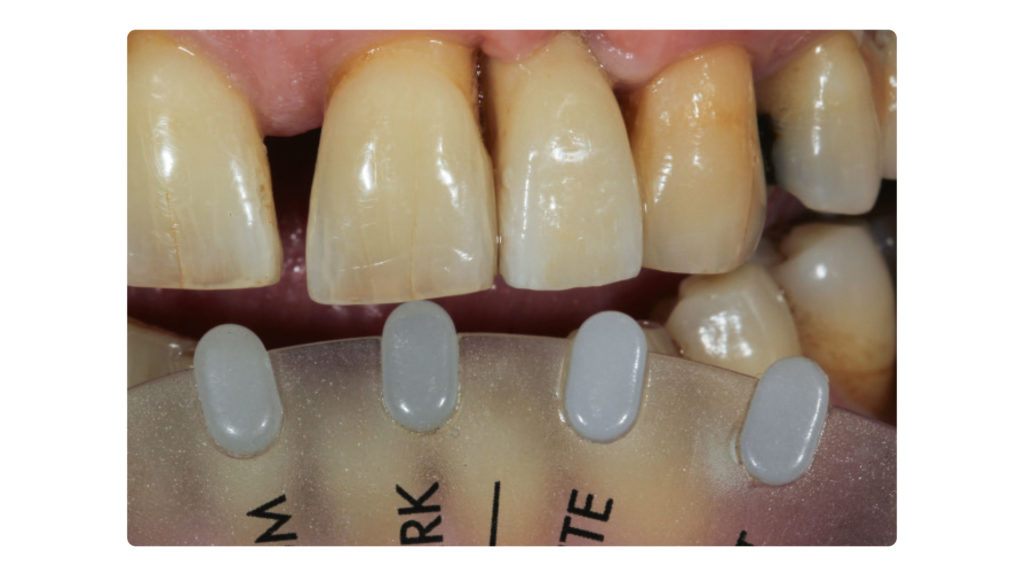

Die Implantatkrone sollte metallkeramisch gelöst werden, was wiederum bedeutete, dass für die entsprechend designte Implantatkrone ein CAD/CAM-gestützt gefertigtes Abutment (vorgefertigt, Schweden & Martina) mit einer Metallkeramik (Ceramco 3, Dentsply Sirona) verblendet werden musste. Es wurde eine zementierte Lösung gewählt, weshalb es keinen Schraubenkanal gab und somit keine Probleme mit dessen Austritt gelöst werden mussten. In den Abbildungen 6a und 6b sind die DSLR-Aufnahmen des Behandlers dargestellt. Die Referenzfarbmuster vermitteln die ungefähre Zahnfarbe, aber nicht alle Informationen und Merkmale, die für die Rekonstruktion des natürlichen Zahns vonnöten sind. Indem man die Belichtung reduziert und den Kontrast sowie die Brillanz in einem Bildbearbeitungsprogramm wie Lightroom (Adobe) erhöht, lässt sich die Histoanatomie des natürlichen Zahns besser darstellen (Abb. 6c).

Auf Wunsch des Patienten sollte der zu rekonstruierende laterale Schneidezahn die Charakteristika des mittleren Inzisiven 21, also seines direkten Nachbarzahns aufweisen. Normalerweise hätte man sich an dem noch verbliebenen lateralen Schneidezahn im ersten Quadranten orientiert, doch leider war auch dessen Zustand nicht ideal, sodass auch dieser in Bälde rekonstruiert werden sollte (Abb. 7a und b). Bei der eingehenden Betrachtung des Zahns 21 stellten wir zwar eine gewisse Ähnlichkeit mit den vom Zahnarzt gewählten Farbmusterzähnen fest, erkannten aber auch relevante Unterschiede. Aus diesem Grund starteten wir die laborseitige Analyse mit polarisierten Aufnahmen (Abb. 8a und b). Da der Patient 49 Jahre alt war, suchten wir gezielt nach charakteristischen Merkmalen natürlicher älterer Zähne und und wurden auch fündig.